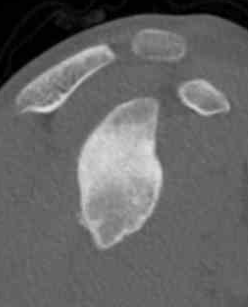

Reverse Hill Sachs / Posterior bony Bankart / Glenoid retroversion

CT

Hill Sachs lesion / posterior bony bankart / glenoid retroversion